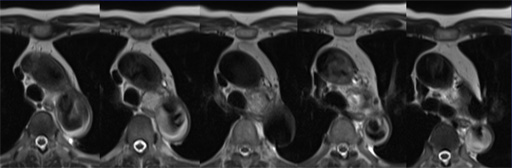

(dynamic study) 図12 DWI (b=500), ADC map

図12 DWI (b=500), ADC map